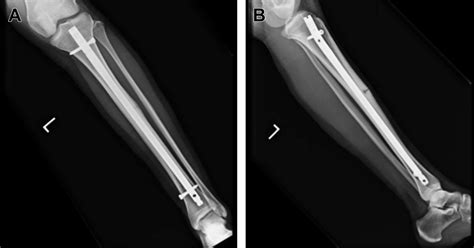

The cornerstone of treating a stress fracture is offloading. You must remove the stimulus that caused the fracture to allow the bone to heal. The recovery process is generally broken down into several distinct phases:

1. Rest and Offloading

The initial phase involves stopping the aggravating activity completely. Depending on the severity of the fracture, your doctor may recommend the use of crutches or a walking boot to offload the tibia and reduce pain during daily movement. This phase can last anywhere from 6 to 12 weeks depending on the location of the fracture and individual healing capacity.